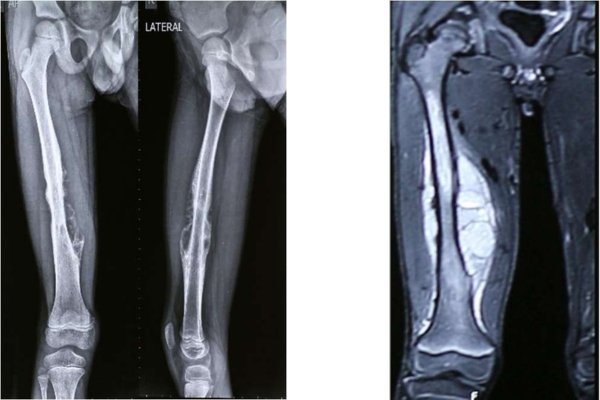

A male patient of 7-year-old hailing from Mumbai, Maharashtra, a student, was diagnosed with Periosteal Ewing`s Sarcoma of Right femur. Patient underwent Neoadjuvant Chemotherapy as part of treatment protocol.

After 9 cycles of NAC, shrinkage of soft tissue mass and bone edema was noted. There was resolution of periosteal reaction as well, all pointing to a favorable response to chemotherapy.

Dr. Manish Agarwal, India’s leading Onco Orthopedic surgeon in Mumbai, Maharashtra being a pioneer in treated tumor bone/ECRT aided surgeries studied medical history, imaging and histopathology reports. It was decided to proceed with ECRT line of treatment. The challenge was to salvage growing epiphyses in this 7 year-old boy’s femur thus using patient specific cutting guides and patient specific femur implant. Incredible team discussed with Dr. Agarwal, the designing and entire manufacturing process. It was initially started with surgical planning and case simulation with the help of US FDA & CE approved Materialise Mimics software by superimposing CT & MRI DICOM data & Anatomical Model. As Anatomical model maintained 1:1 ratio with the anatomy, hence showed excellent detailing of the defect, the model was also used to design jigs & implant on actual bone, which further helped the pre surgical planning. Once the planning was finalized, the surgery was accompanied with not only Customized Implant but also Cutting guides & Jigs. Read more